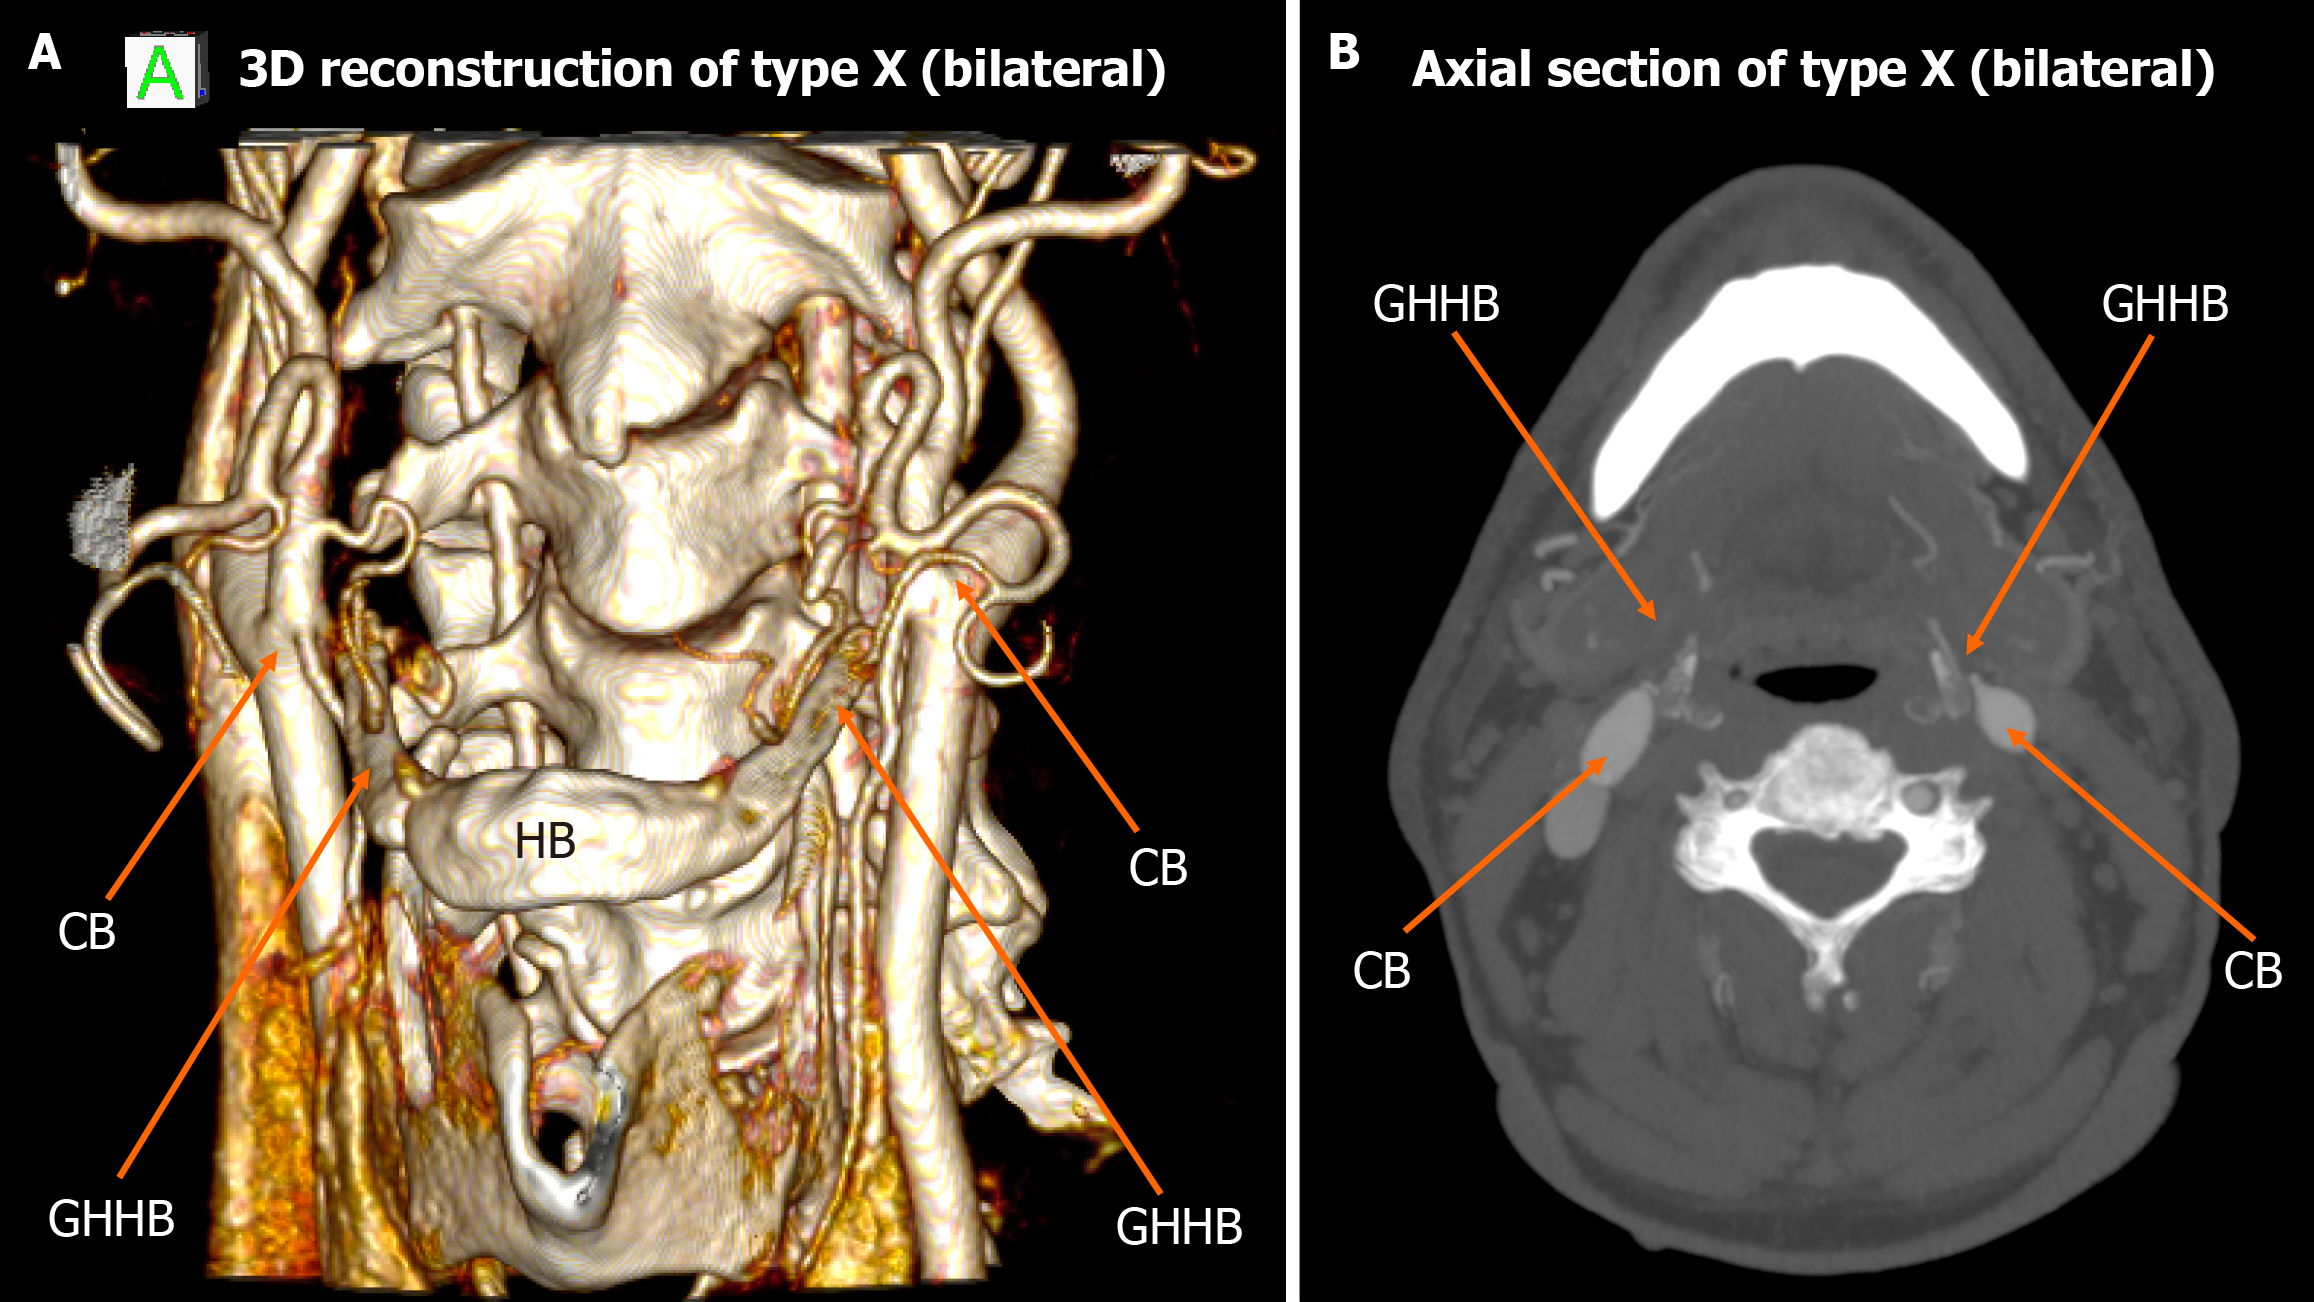

Figure 7 Type X bilateral configuration.

A: 3D reconstruction demonstrating the carotid bifurcation located lateral to the greater horn of hyoid bone on both sides; B: Axial view highlights bilateral type X relationship. CB: Carotid bifurcation; GHHB: Greater horn of hyoid bone; HB: Hyoid bone.